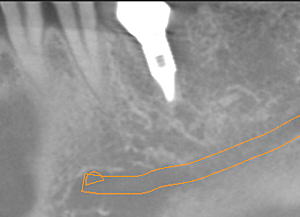

下顎奥歯に埋入したインプラントのCT画像

①の赤線に沿って縦に切断したところです。 パノラマレントゲンでも同じようなものが撮れますが、これほどハッキリと歯の神経(中心部の縦のスジ)が映るのはCTならではです。 |